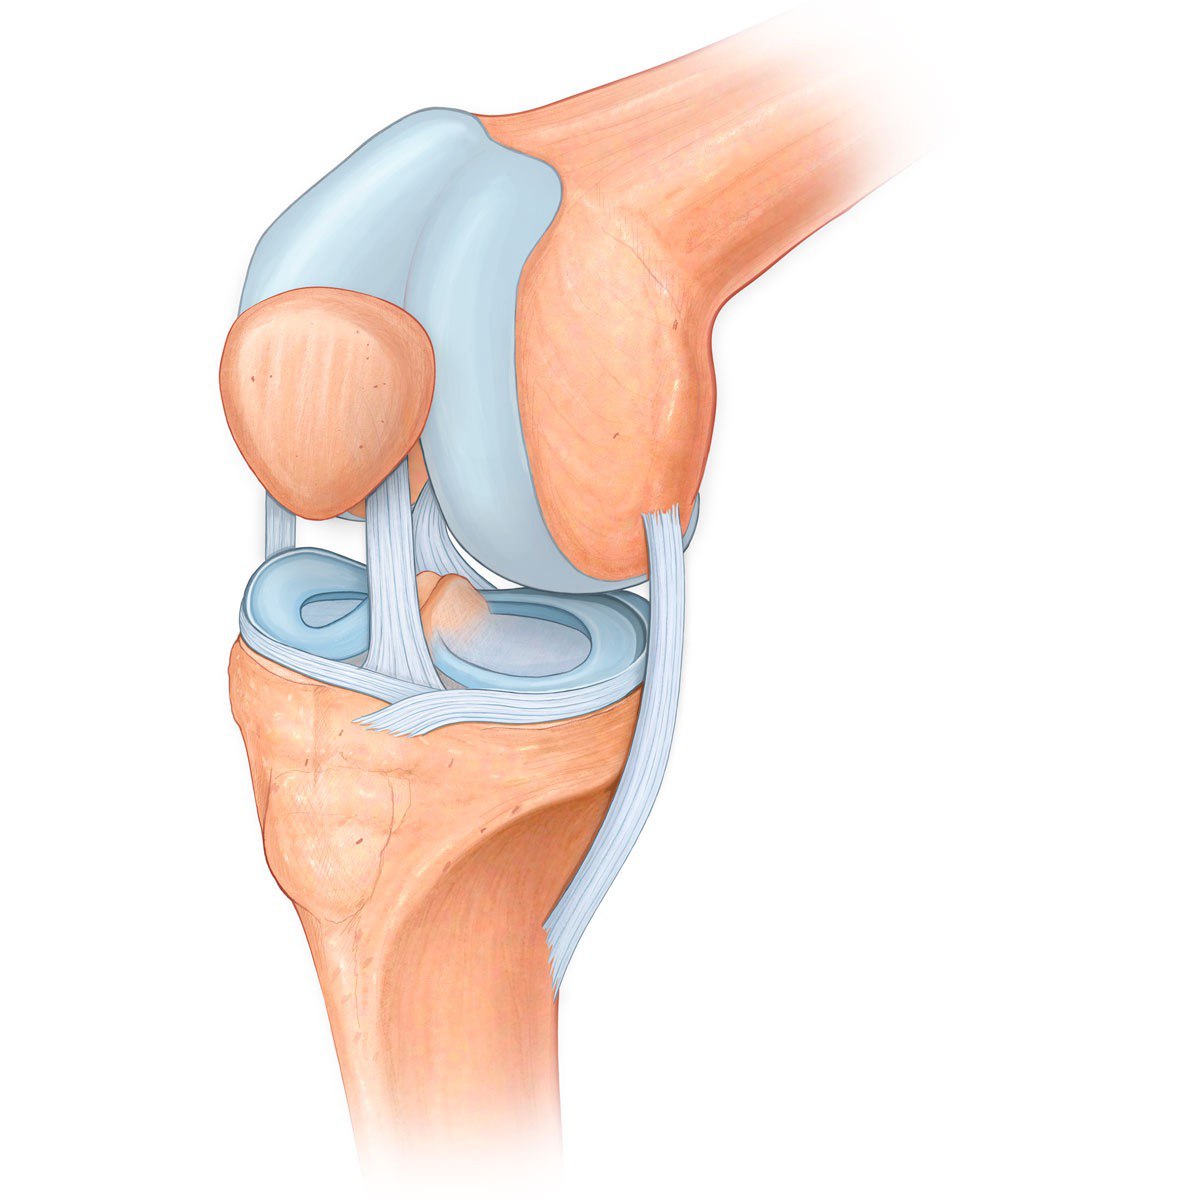

Проблемы с коленным суставом: флоттация и лечение